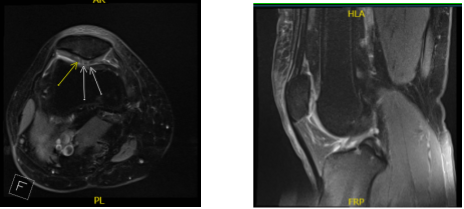

An MRI was done, which showed an osteochondral lesion in the patellofemoral joint. She had no relief with nonoperative treatment. We discussed treatment options and operative surgical management.

MRI Right knee non-contrast